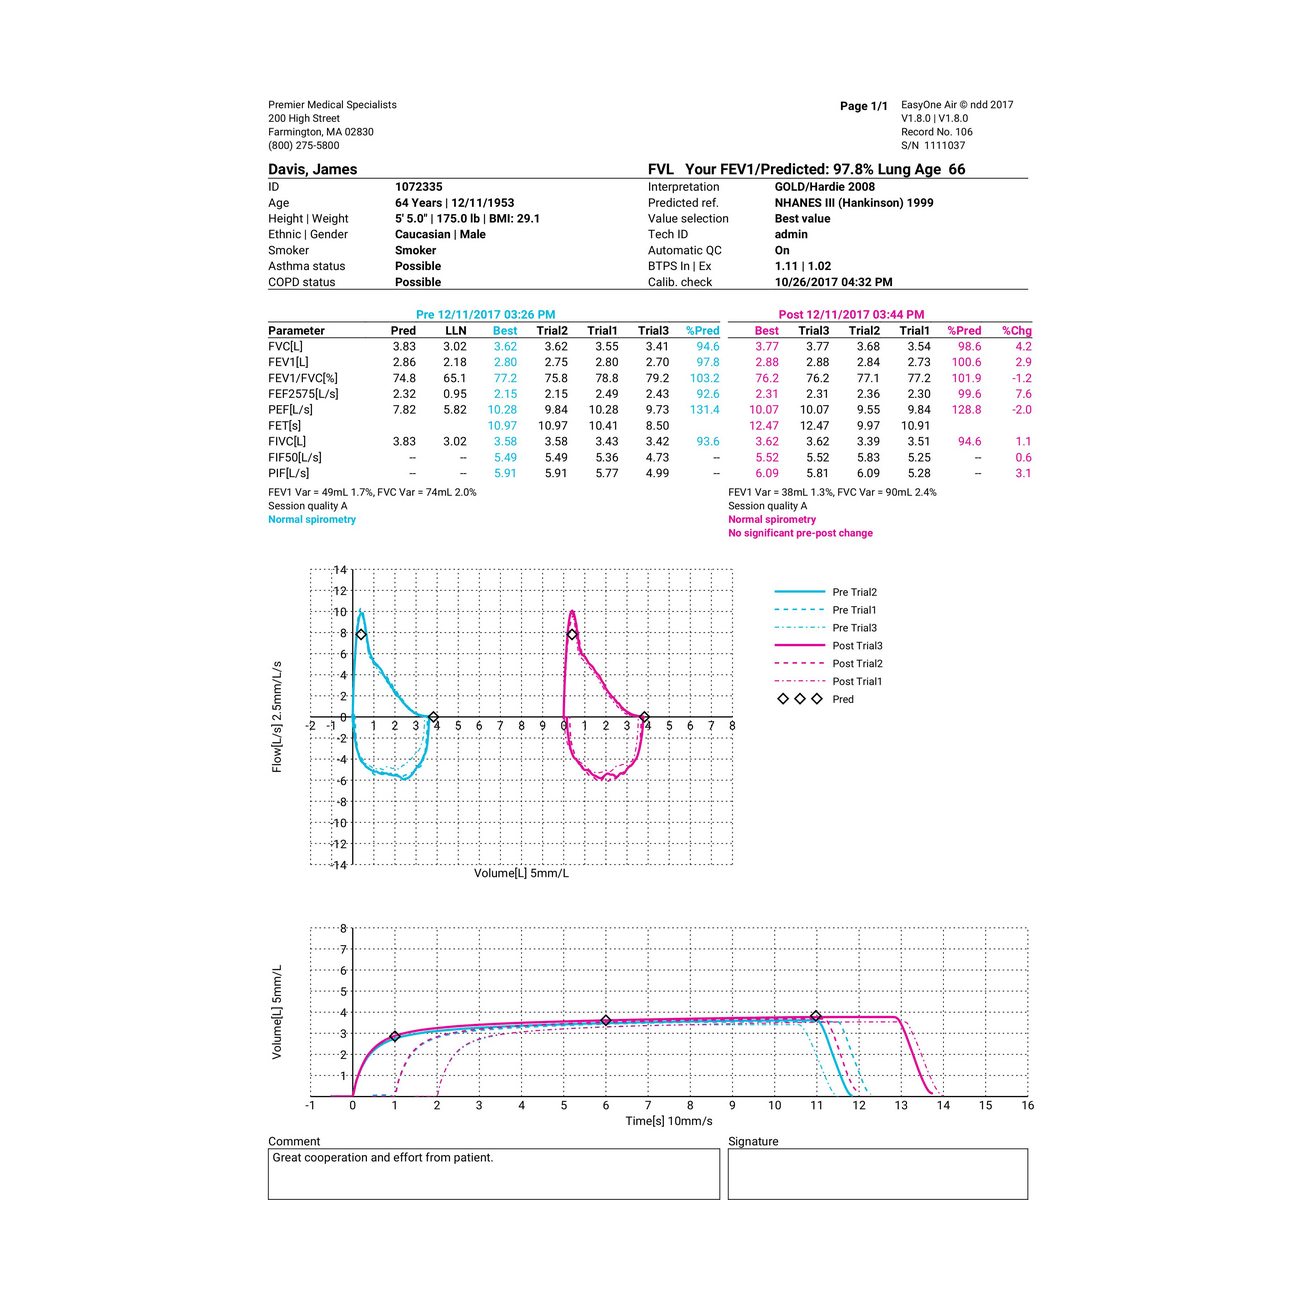

- Datenaustausch über Bluetooth oder USB mit 'EasyOne Connect'-Software

- Einfache Verbindung zum PC für Echtzeit-Grafiken, Datenaustausch und Anbindungen

- Drucken über direkten USB-Anschluss oder via 'EasyOne Connect'